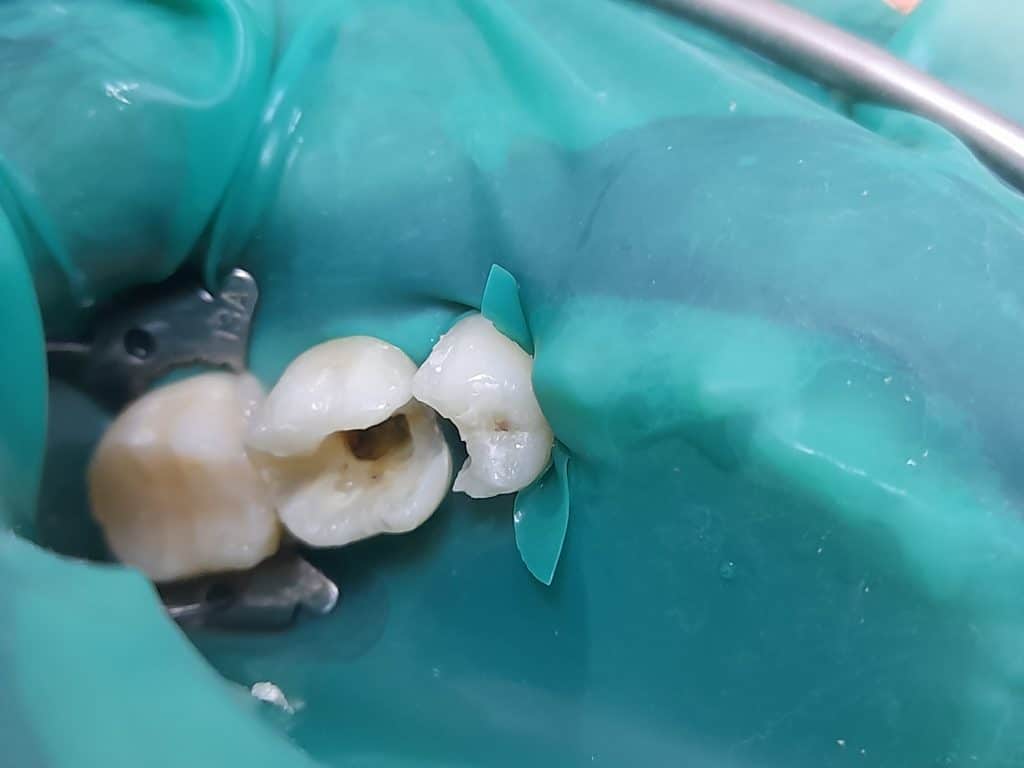

1.1st session: vital pulp therapy, neoputty. tooth 35

Root canal treatment, lateral condensation obturation, resin based sealer. Tooth 36

2. 2nd session: Composite build up, layering technique, tokoyama estellite conventional and bulk fill.